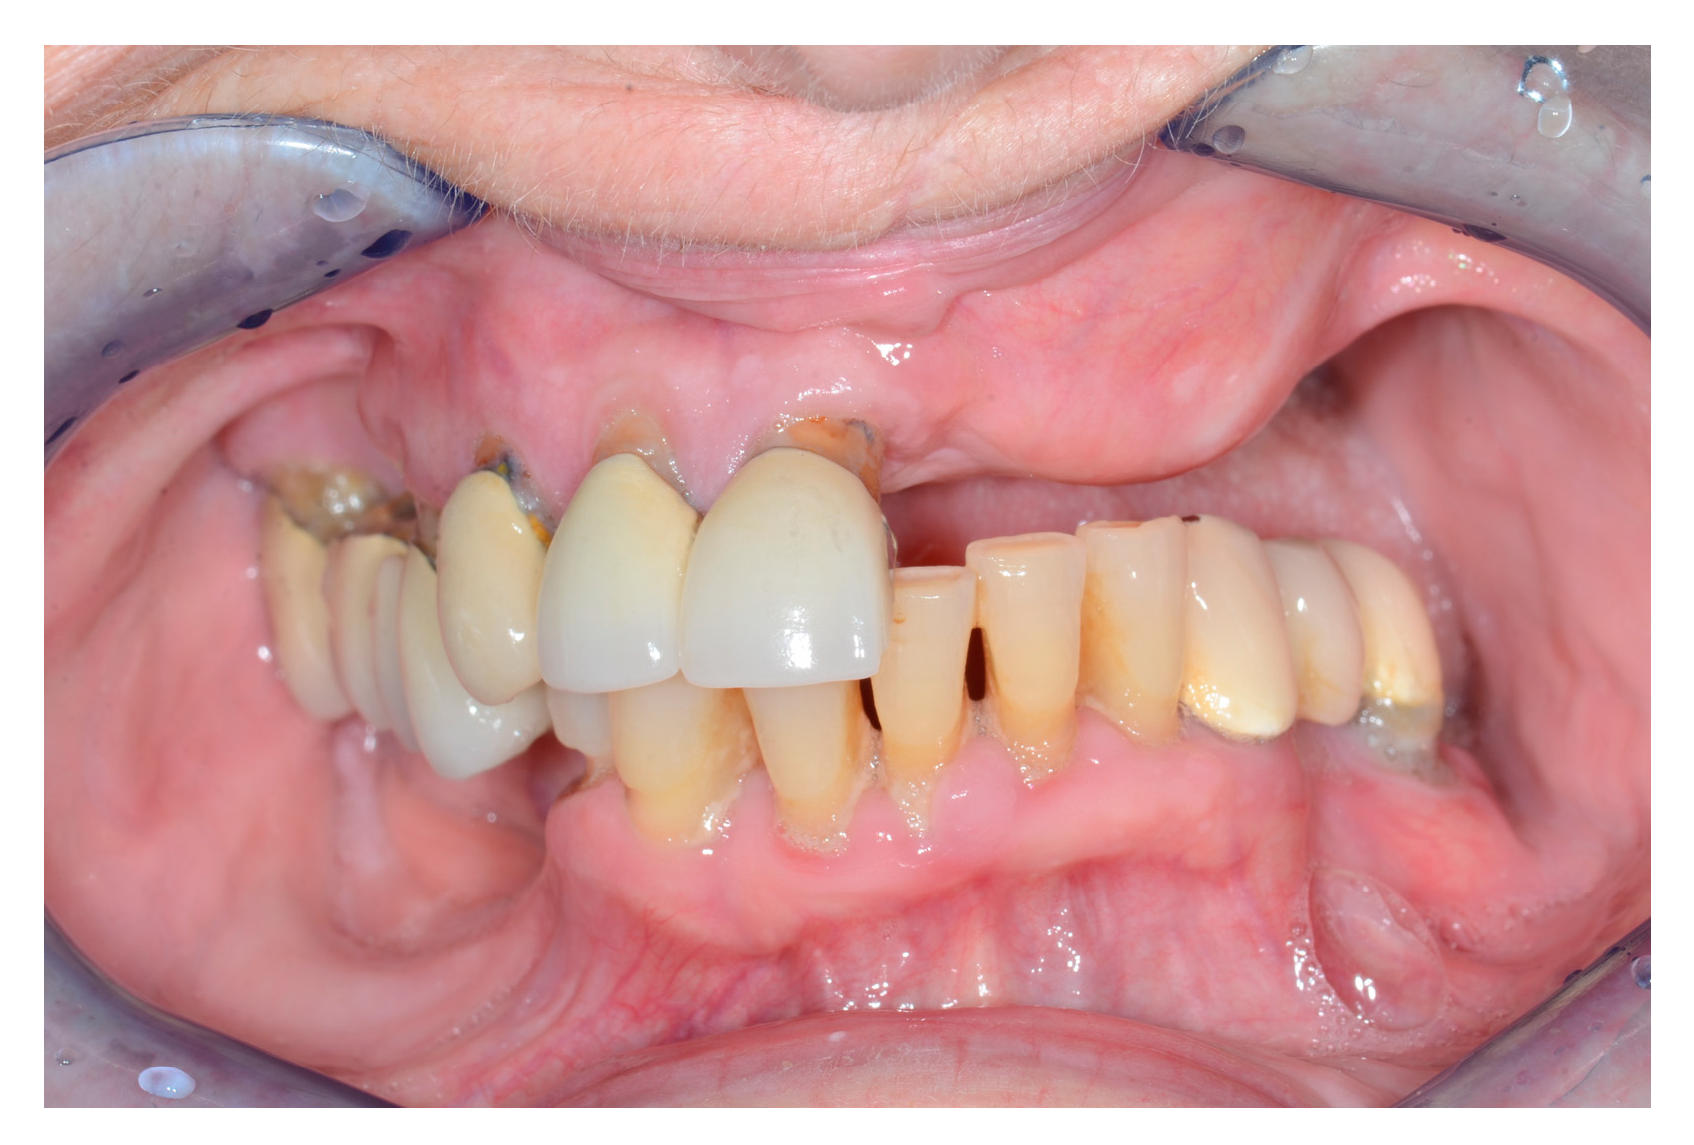

Here, support and volume are required to obtain an aesthetically pleasing and functional reconstruction. A DCIA with internal oblique muscle and skin in conjunction with an MFC (or a perforator flap) can satisfy the above requirements. The DCIA replaces the maxilla, while the MFC reconstructs the orbital walls, as seen in the patient below (Figure 1, Figure 2, Figure 3, Figure 4, Figure 5 and Figure 6).

Figure 1. Patient at presentation after numerous resections and external beam radiotherapy for melanoma of the cheek on the left-hand side. At this stage, the melanoma was infiltrating the orbital floor, the orbital fat and the inferior oblique muscle, the maxilla’s frontal process, the lamina papiracea, and the anterior wall of the maxillary sinus. The eye was dislocated in a cranial position and rotated upwards.

Figure 4. Intraoral view after alveolar ridge reconstruction.